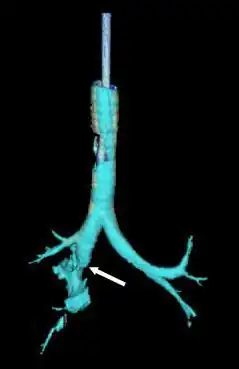

Reconstrução da traqueia e brônquios com tomografia computadorizada mostrando o rompimento do brônquio principal direito com lucência anormal (seta)[1]

Estenose brônquica (seta) duas semanas após cirurgia para laceração traqueobrônquica.[1]

Se tecido de granulação cresce sobre o local lesionado, pode causar estenose da via aérea após uma semana a um mês.[4] O tecido de granulação deve ser excisado cirurgicamente.[26] O diagnóstico tardio de uma ruptura brônquica aumenta o risco de infecção e prolonga a internação.[29] Pacientes com via aérea estreitada podem desenvolver dispneia, tosse, sibilo, infecção respiratória e dificuldade para eliminar secreções.[10] Se o bronquíolo está completamente obstruído, ocorre atelectasia: os alvéolos do pulmão colapsam.[4] O tecido pulmonar distal a um bronquíolo completamente obstruído frequentemente não é infectado. Como está cheio de muco, esse tecido permanece funcional.[22] Quando as secreções são removidas, a porção afetada do pulmão geralmente funciona quase normalmente.[30] No entanto, infecção é comum em pulmões distais a um bronquíolo parcialmente obstruído.[22] O tecido pulmonar infectado distal a uma estenose pode ser danificado, e sibilos e tosse podem surgir devido ao estreitamento.[15] Além da pneumonia, a estenose pode causar bronquiectasia, com dilatação dos brônquios.[22] Mesmo após a restauração de uma via aérea com estenose, a perda de função pulmonar pode ser permanente.[22]